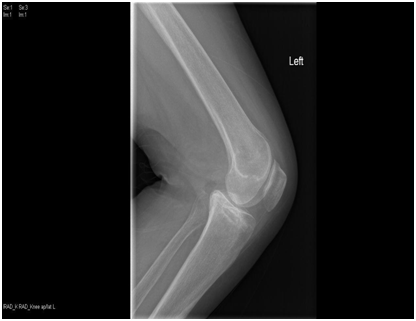

We present a 77 years old Caucasian female with spontaneous onset of pain in both knees for several weeks before presenting to the casualty then to our fracture clinic. There was no history of trauma. The patient is known to have Rheumatoid arthritis (RA) for over 30 years and has been on Bisphosphonate treatment (Alendronate) for over 24 months following the diagnosis of osteoporosis by DEXA scan. Plain radiographs showed subtle linear areas of sclerosis bilaterally in her proximal tibiae (Figure 1 & 2). Magnetic resonance imaging confirmed the presence of extra-articular linear high signal intensity change on T1, T2 with surrounding marrow edema consistent with insufficiency fractures in these areas as well as her right distal femur (Figure 3). These fractures were treated successfully with activity modification and weight bearing in a hinge knee brace as symptoms allows for six weeks along with physiotherapy input. Alendronate was stopped and Teriparatide (Recombinant PTH) was started.

Figure 1 AP & lateral radiograph of the left tibia showing an insufficiency fracture with osteosclerotic changes at the medial proximal tibia.